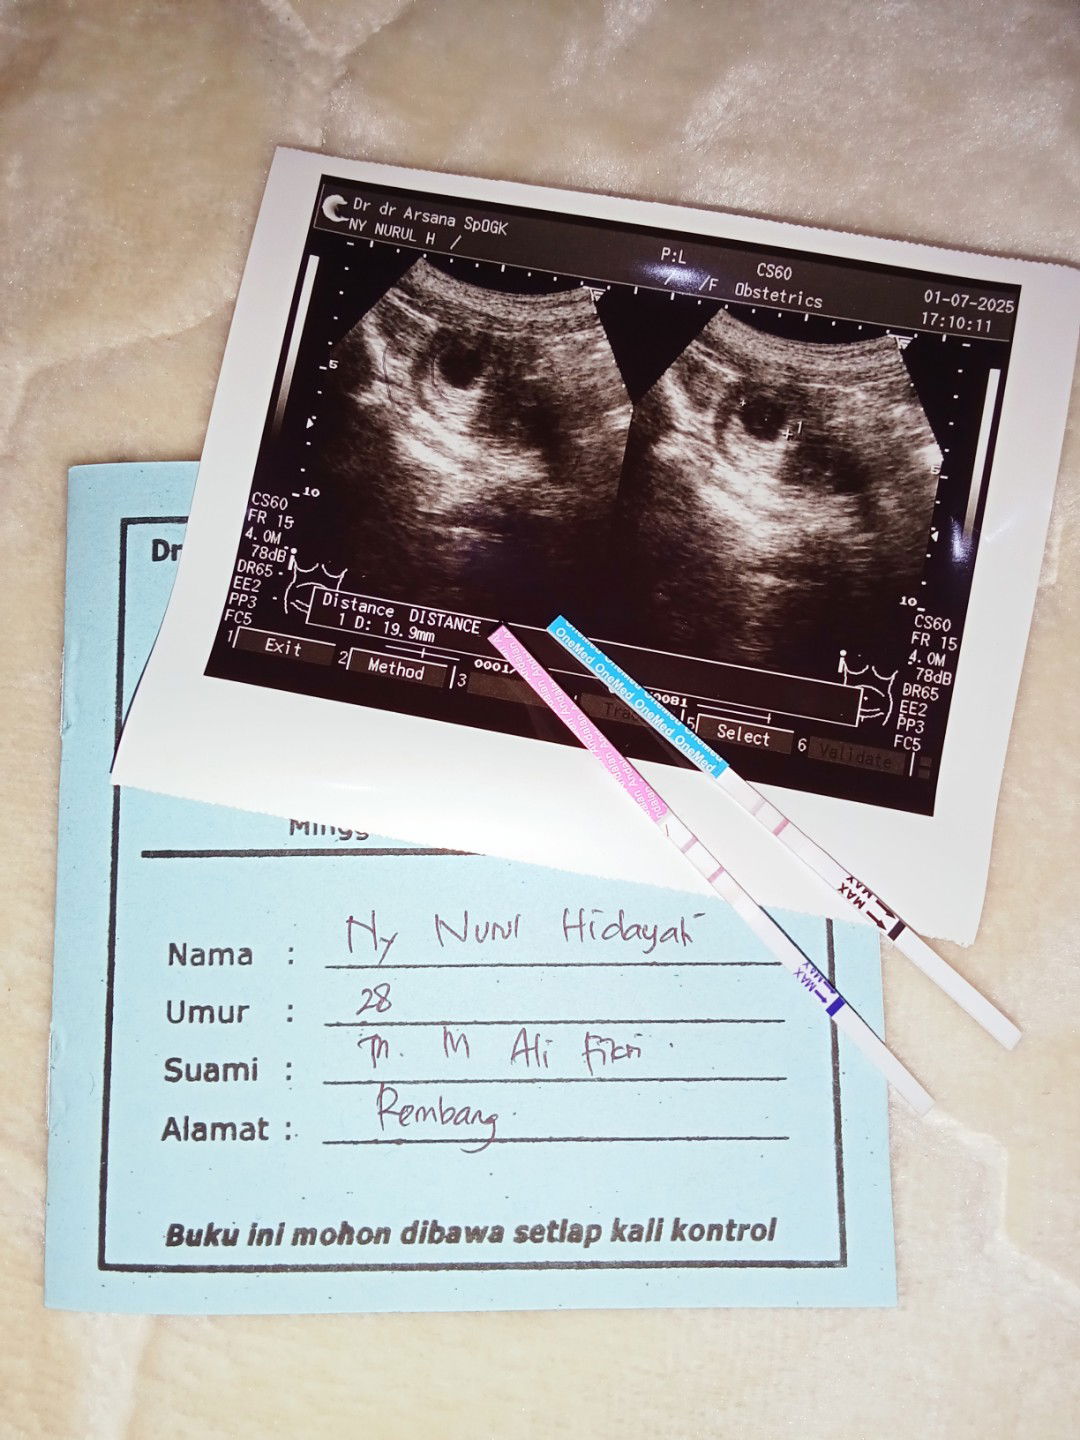

Bund. Ada yg pernah hamil flek warna coklat tua tapi tiap hari keluar di kehamilan 5 week?

sya juga flek sudah mau 3 mingguan.. keluar warna coklat. sudah USG dan minum obat penguat sudah mengurangi aktivitas.. 2 minggu lagi disuruh cek USG. ini kehamilan pertama.. semoga sehat semuanyaπ€²π»